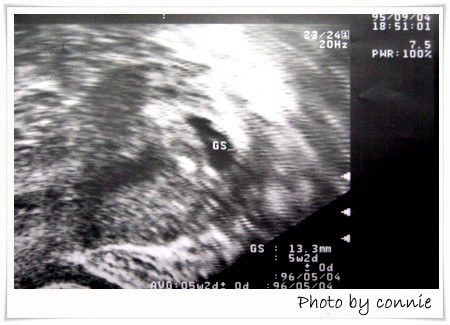

自從19日在診所驗出懷孕以後

懷孕的症狀突然的全部都來了

因為有些初期著床的出血症狀

所以假日幾乎都躺在床上